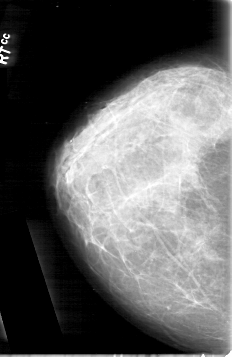

D_4092_1.RIGHT_MLO

RIGHT_CC LINES 5341 PIXELS_PER_LINE 3466 BITS_PER_PIXEL 12 RESOLUTION 43.5 NON_OVERLAY

RIGHT_MLO LINES 5251 PIXELS_PER_LINE 3526 BITS_PER_PIXEL 12 RESOLUTION 43.5 NON_OVERLAY